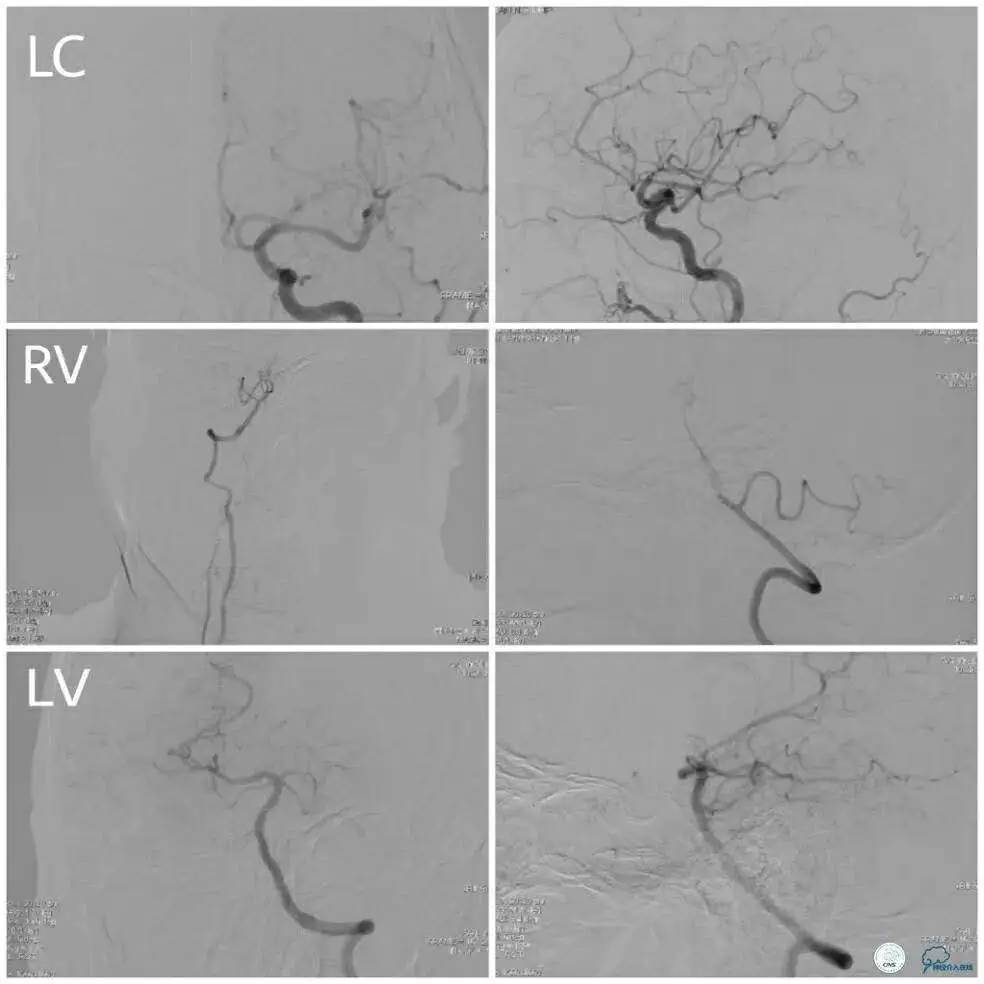

同侧大脑后动脉及大脑前动脉提供的软脑膜动脉侧支代偿欠佳(图1及图2)。

术中于右大脑中动脉M1段置入无Tip的Enterprise支架(4.5 mm×22 mm)1枚,释放后显示狭窄明显改善,前向血流3级(图3)。

半年后复查DSA示右侧大脑中动脉支架内血流通畅,前向血流3级(图4)。